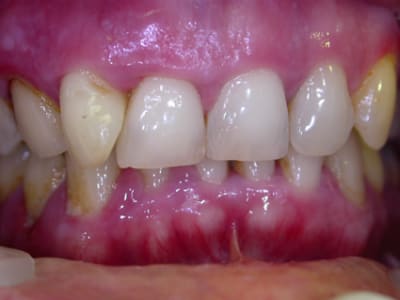

Oui, on peut trouver des études sur la sensibilité dentinaire après curetage, on a tous vu des photos de curetages agressifs ou répétés qui laissent les dents fragilisées.

Et les concepts évoluent, on ne cherche plus à éliminer les toxines imprégnées dans le cément mais à éradiquer la cause ; du coup les méthodes changent, on garde le cément pour la réattache et on cible les bactéries responsables.